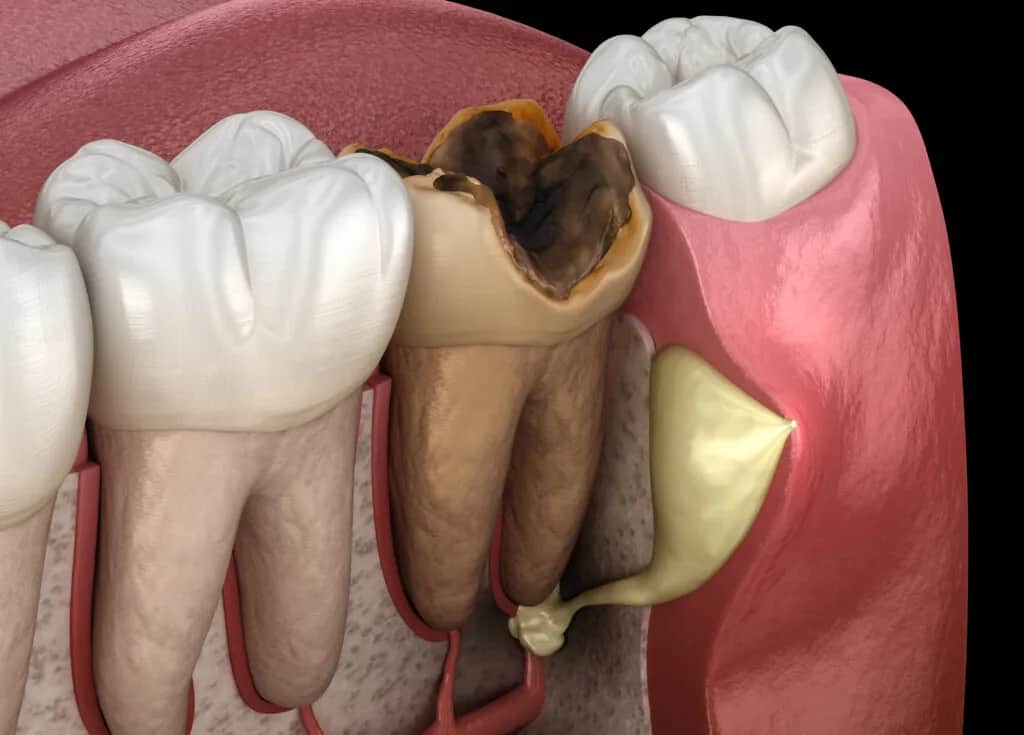

Perforacja kanału zęba, nazywana również przebiciem, to nic innego jak niepożądane połączenie, które powstaje między systemem kanałów korzeniowych a otaczającymi ząb tkankami przyzębia czyli kością i ozębną. Może być ona jatrogenna, co oznacza, że powstała w wyniku działania lekarza podczas zabiegu, lub patologiczna, na przykład w wyniku zaawansowanej próchnicy lub procesów resorpcyjnych niszczących tkanki zęba. Niezależnie od przyczyny, jest to jedno z poważniejszych powikłań leczenia endodontycznego, które wymaga natychmiastowej uwagi i precyzyjnego działania.

Ignorowanie nietypowych objawów po leczeniu kanałowym jest niezwykle ryzykowne. Perforacja, jeśli pozostanie nieleczona, staje się wrotami dla bakterii, prowadząc do rozwoju przewlekłego stanu zapalnego w otaczających tkankach. To z kolei może skutkować postępującym zniszczeniem kości wokół zęba, tworzeniem się ropni, przetok, a w konsekwencji do konieczności usunięcia (ekstrakcji) zęba, który mógłby zostać uratowany. Wczesne rozpoznanie i interwencja są kluczowe dla zachowania zęba i uniknięcia poważniejszych problemów.

- Zaawansowana próchnica: Głębokie ubytki próchnicowe mogą osłabić struktury zęba i prowadzić do patologicznych perforacji.

- Procesy resorpcyjne: Są to procesy, w których tkanki zęba (korzeń, zębina) są stopniowo niszczone przez komórki organizmu, co może prowadzić do powstania ubytków i perforacji.

- Kiedy ekstrakcja jest nieunikniona? Niestety, w niektórych przypadkach, mimo wszelkich starań, perforacja może prowadzić do nieodwracalnych uszkodzeń. Nieleczona perforacja lub taka, która nie reaguje na leczenie, prowadzi do przewlekłego stanu zapalnego, rozległego zniszczenia kości i w konsekwencji do konieczności usunięcia zęba. To ostateczność, której staramy się za wszelką cenę uniknąć.